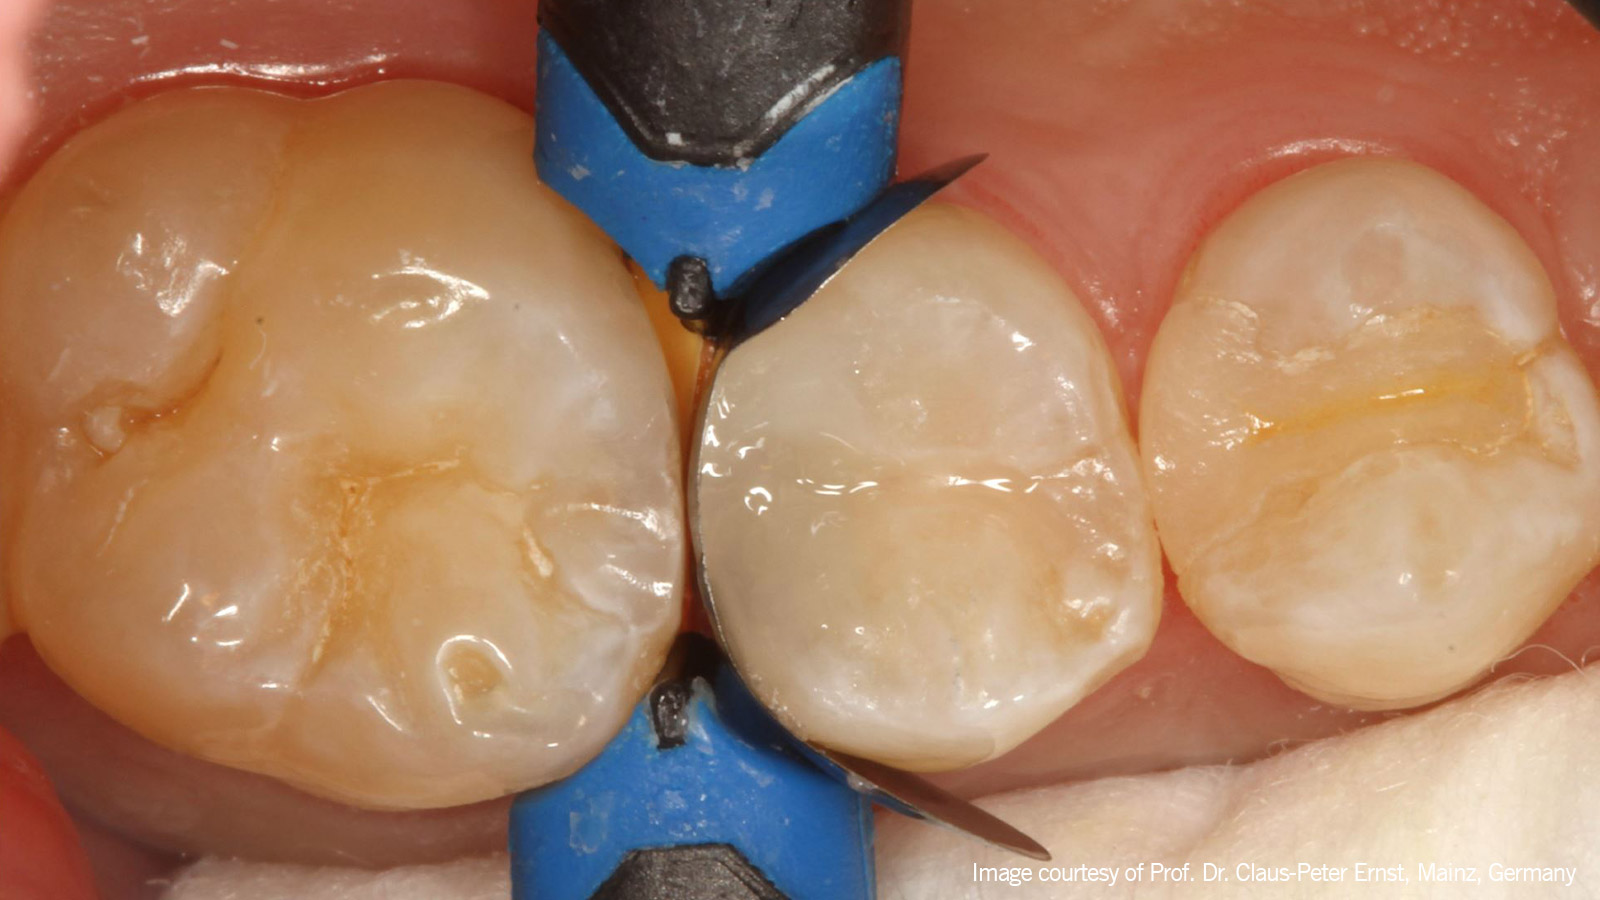

The first layer

De eerste laag in de proximale box en in de uitgebreide occlusale fissuur werd gecreëerd met Venus Bulk Flow ONE in een "klassieke" flow laagdikte van 1-2 mm.

self-adapting colour ONE

Vervolgens werd Venus Pearl in de zelfaanpassende kleur ONE als toplaag gebruikt.